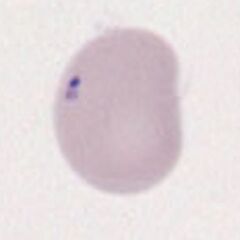

Grey/blue inclusions of varying size, generally small and usually (but not always) near the edge of erythrocytes. Frequently they form clusters of 2 or 3 inclusions. They are darker than Howell Jolly bodies.

Images Small numbers (generally 1-5) small dark purple or grey inclusions, peripherally distributed and often appearing to be in groups. The red cell is often normal in size and shape but may show signs of the intrinsic cause (e.g. dysplasia, iron-loading conditions or splenectomy).

Pappenheimer bodies should be distinguished from other basophilic intracellular inclusions. Distinction from Howell Jolly bodies may cause particular problems, as both bodies may arise together, but generally are distinguished by attention to colour, texture and position. Platelets or stain debris overlying the erythrocyte may occasionally cause confusion, particularly the latter (see the specific section on artefacts). If there is doubt then perform an iron stain to confirm the iron content of the Pappenheimer body (see images).